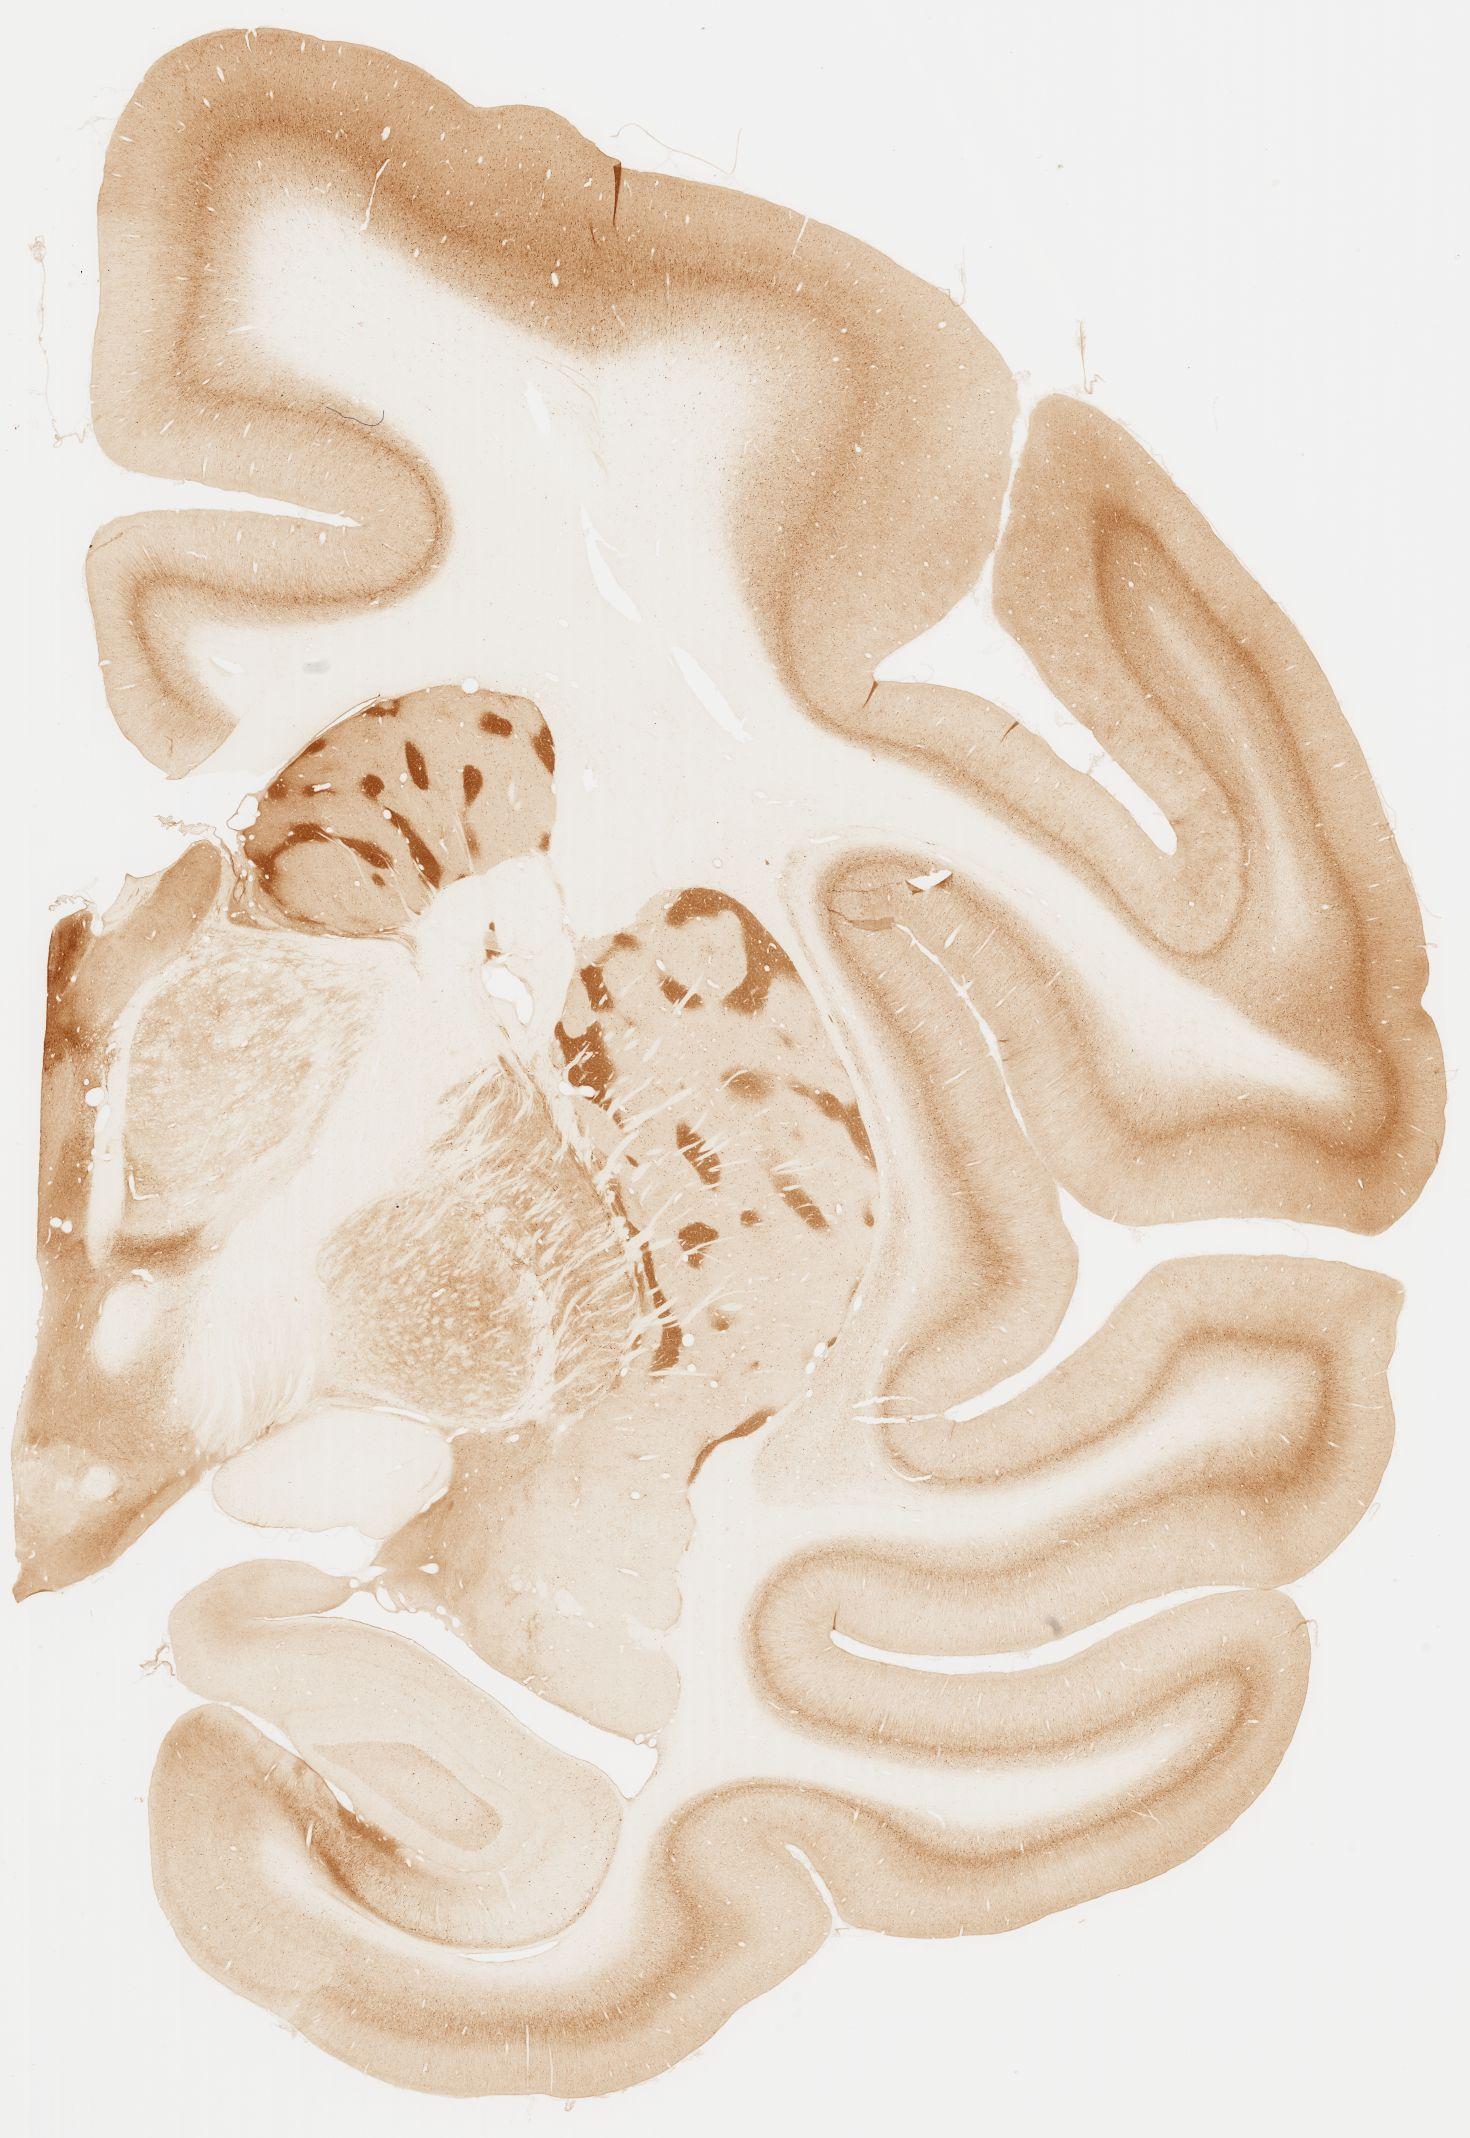

Datasets -> Macaca Fascicularis -> KChIP1, (Potassium Voltage-Gated Channel-Interacting Protein 1), coronal, immuno, Whole-Brain, adult

[ Metadata ]   ·   Source: Edward G. Jones

Displaying Sections 41 thru 80 of 92 Sections for this Dataset